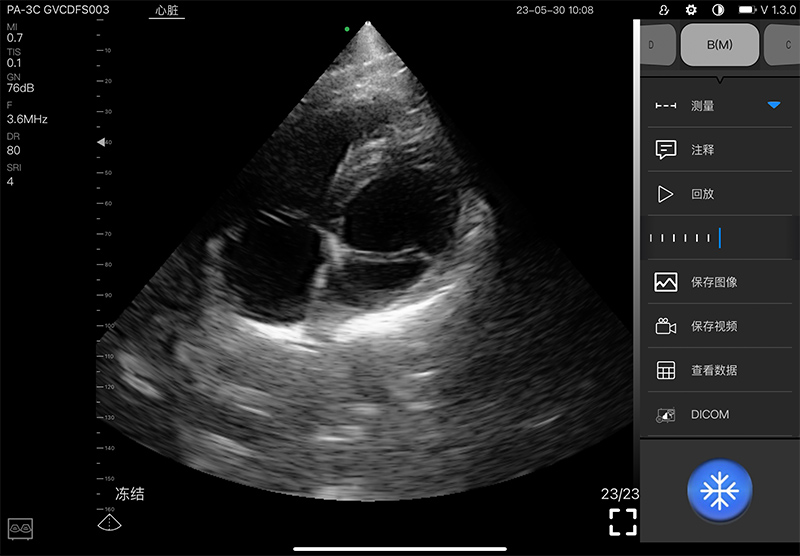

- Display mode: B, B/M, and Color, PW, CW, PDI

- Frequency: central 2.8MHz, cardiac reverse harmonic

3.6mhz, and the transcranial fundamental 2.2MHz